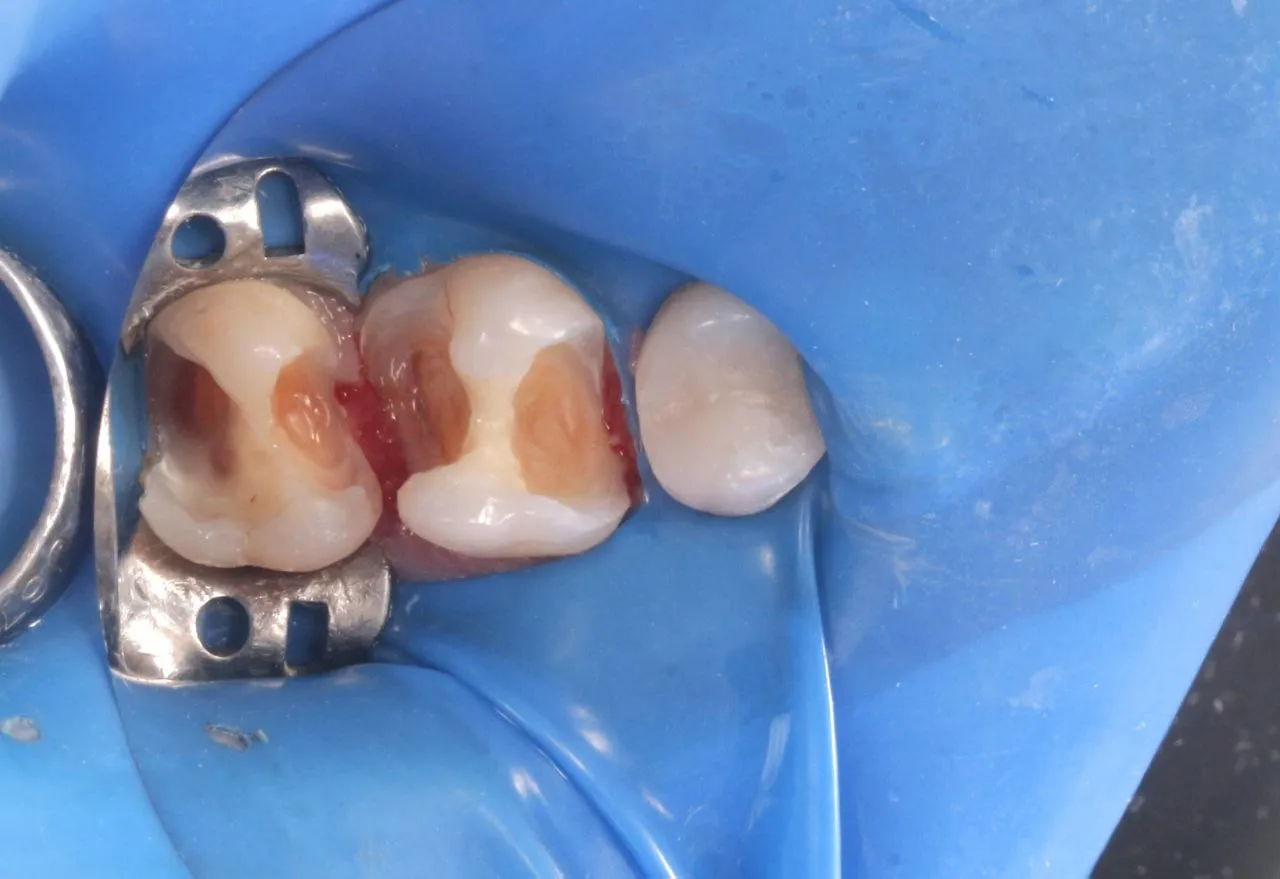

Лікування глибокого вторинного карієса зубів 17 та 16

Лікування вторинного карієсу в зубах 47 та 45